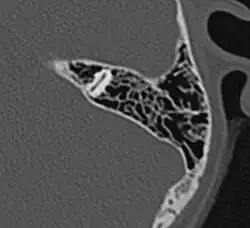

Развитие пневматизации околоносовых пазух и ячеек сосцевидных отростков достигается мешковидным выпячиванием слизистой оболочки полости носа и среднего уха в компактное вещество кости. Окончательное развитие околоносовых пазух у человека достигается к 20—25 годам. Некоторые животные не имеют воздухоносных костей (тюлени, киты), у некоторых объём пневматизации, напротив, выше, чем у человека. Развитие пневматизации височной кости завершается к пяти-шести годам; наиболее выражена пневматизация ячеек сосцевидных отростков. Размеры ячеек различаются; так, у некоторых индивидуумов сосцевидный отросток остаётся практически не пневматизированным, что, вероятно, обусловлено предшествующими частыми воспалительными процессами в среднем ухе; у других, напротив, пневматизированные ячейки могут распространяться в чешуйчатую часть височной кости, скуловой отросток или к вершине пирамиды.